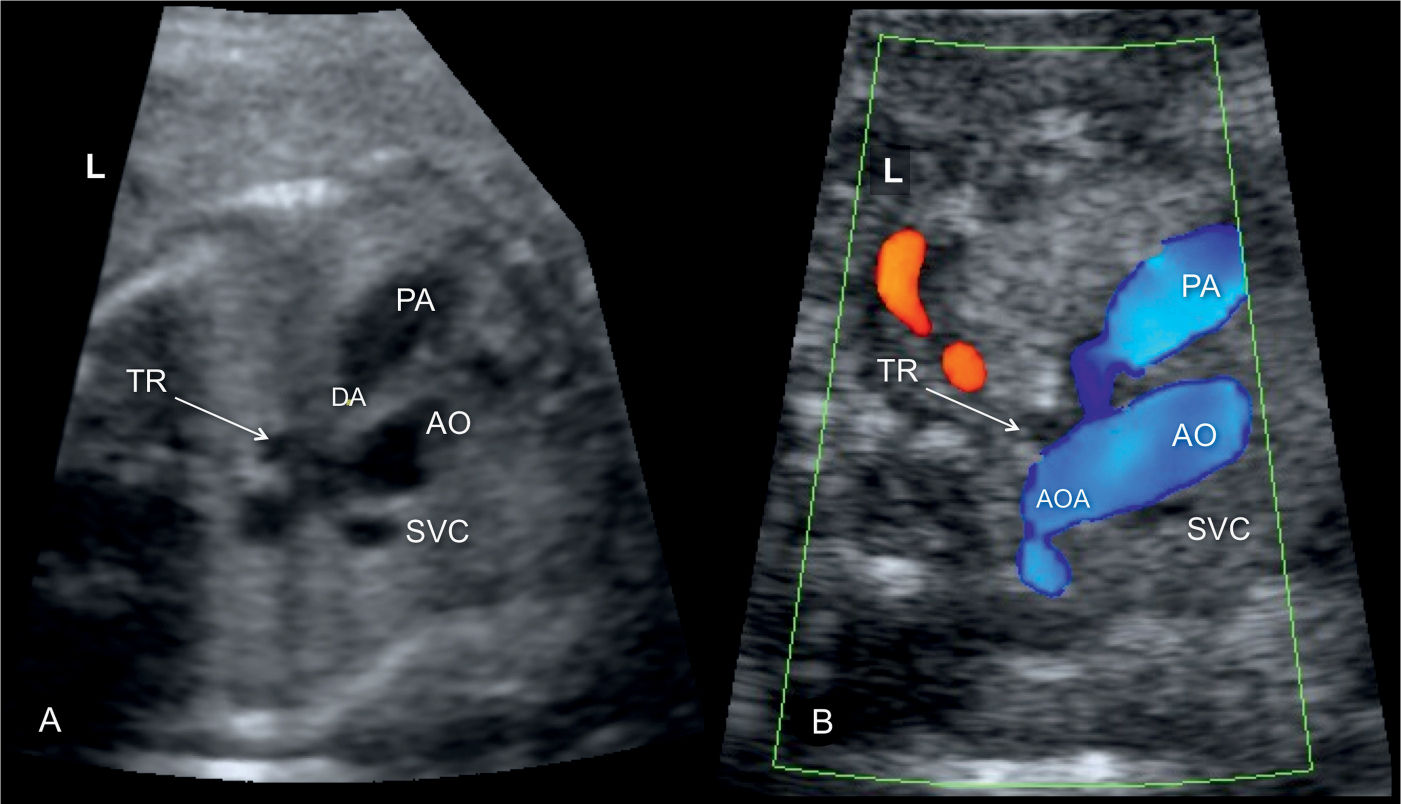

Right Aortic Arch With Mirror Image Branching